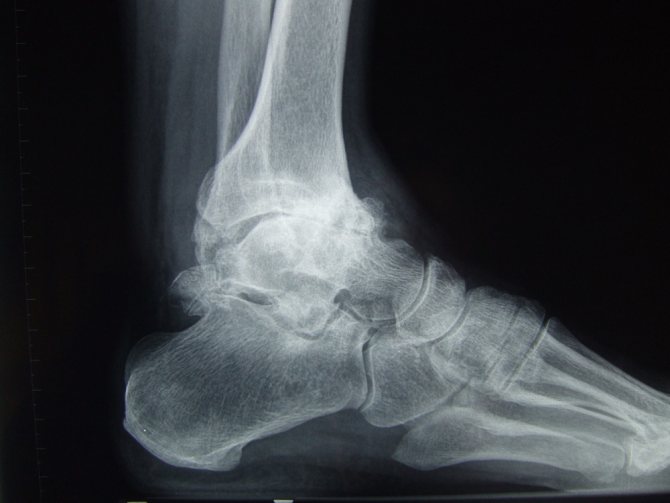

Лабораторные исследования крови при этом заболевании являются малоинформативными. Однако чтобы подтвердить диагноз, врач может назначить ряд инструментальных исследований, позволяющих выявить характер имеющихся изменений в структуре сустава. Наиболее часто для оценки состояния сочленения назначается рентгенография, но могут применяться и другие методы визуализации.

При остеоартрозе голеностопа второй степени на рентгенологических снимках чётко просматриваются остеофиты. При осмотре видна деформация сочленения, округлые уплотнения в области сустава. При пальпации определяются околосуставные бугорки. Сам сустав часто увеличивается в размере, объем активных движений в нем уменьшается.

При третьей степени на снимках уже видно умеренное сужение суставной щели. У человека деформируется стопа, меняется походка, усиливается выраженность симптомов болезни.

Четвёртую степень диагностируют при значительном сужении или полном исчезновении суставной щели и полном отсутствии движений в сочленении.

Проявление симптоматики зависит от степени артроза голеностопа. Заболевание может проходить четыре стадии развития, которые выявляются с помощью рентгеновского метода исследования.